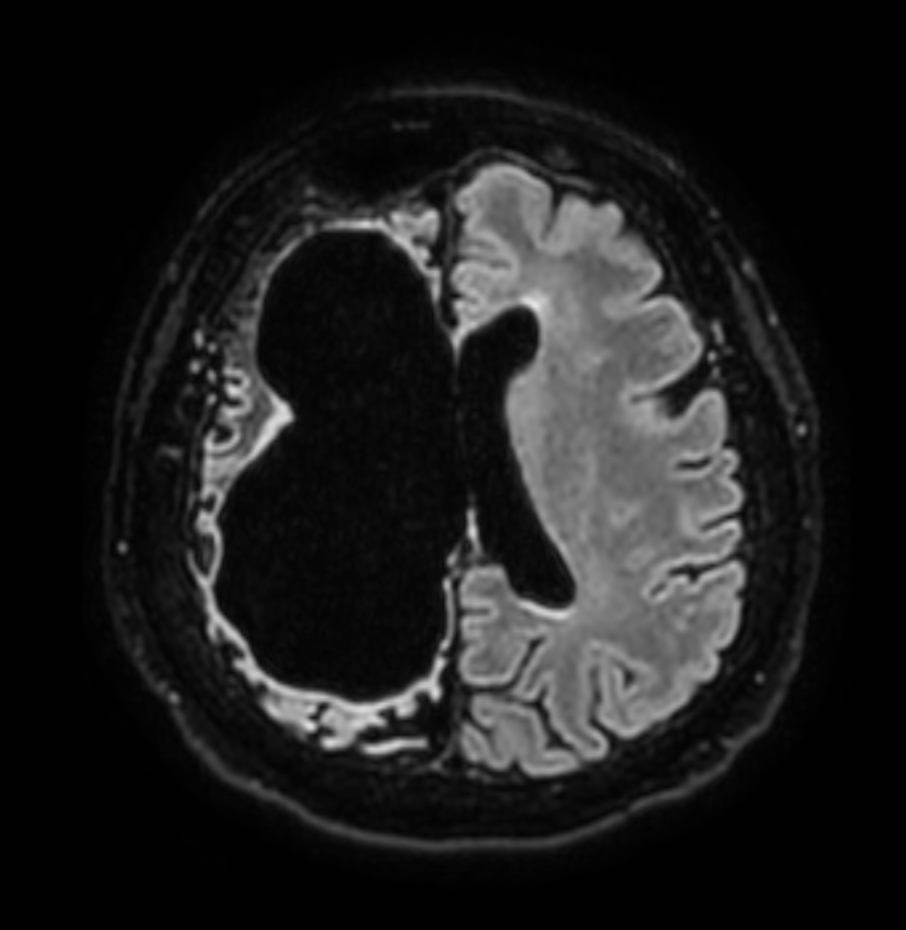

Axial T2w TSE

Axial T2w FFE